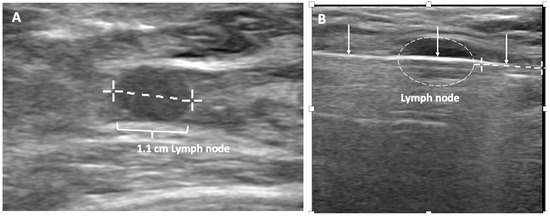

Ultrasound of the axilla. Axillary ultrasound permits the detection of abnormal appearing lymph nodes that might not be detected on physical examination, mammography, or breast MRI. Axillary ultrasound is the most sensitive imaging study for the detection of subtle changes in the shape or thickness of a lymph node cortex that might indicate the presence of lymph node metastasis (Figure 3). Detection of suspicious lymph nodes determines clinical cancer stage and requires a specific plan to manage the possibility of lymph node metastasis.

Figure 3.

Hash marks outline abnormal appearing axillary lymph node measuring 1.5 cm in maximal diameter. Paired “+” marks indicate the span of a 0.4 cm area of focal cortical thickening that is suspicious for a metastatic deposit within the lymph node.